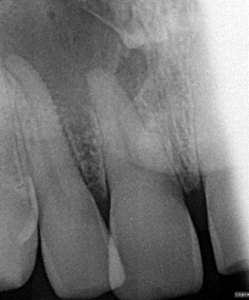

Root Canal / Retreatment

Clinical Cases